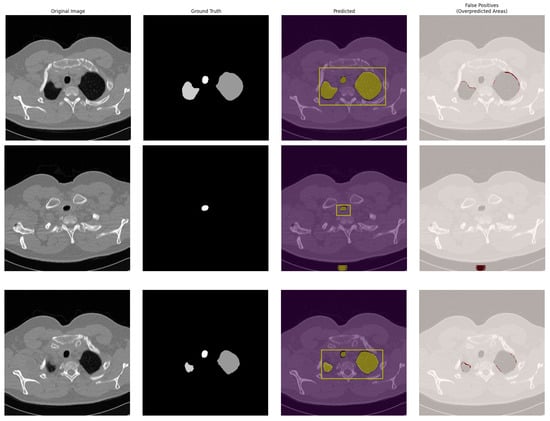

4.2. Qualitative Results

- Tissue Density Similarity: Anatomical structures with attenuation coefficients (Hounsfield units) similar to the targeted ROI can induce classification errors. This densitometric ambiguity is particularly pronounced in transition zones between soft tissues and vascular structures. For example, blood vessels, scar tissue, and areas of fibrosis can exhibit Hounsfield values that overlap with those of lung nodules, especially part-solid or ground-glass nodules. This overlap makes it challenging for the model to solely rely on intensity information for accurate differentiation, leading to false-positive detections in regions with dense vasculature or fibrotic changes.

- Morphological Characteristics: The presence of anatomical structures with geometric characteristics similar to irregular or hidden ROI can generate segmentation errors. The model may incorrectly interpret these formations as potential ROI. In advanced lung disease, ROI such as tumors or affected lung parenchyma can exhibit highly irregular shapes and may be partially obscured or hidden by surrounding diseased tissue, pleural effusions, or consolidation, as frequently observed in the PleThora dataset. SALM, trained primarily on datasets with relatively well-defined ROI like LUNA16, may struggle to accurately delineate these highly irregular and poorly defined ROI in advanced pathological cases. The model’s reliance on shape features learned from less complex examples might lead to under-segmentation or inaccurate boundary delineation when confronted with the complex and atypical morphologies characteristic of advanced lung pathologies. This is further compounded by the fact that, in diseased lungs, the contrast between the ROI and the surrounding abnormal tissue may be reduced, making morphological differentiation even more challenging for the model.

- Positional Encoding Limitations: Overpredictions can result from an imperfect capture of three-dimensional spatial relationships, despite the use of modified positional encoding. Peripheral areas of anatomical structures, where intensity gradients are less pronounced, are particularly susceptible to misclassification. While our modified 3D positional encoding enhances spatial awareness, it is not perfect. In regions where anatomical structures are complex or boundaries are ill-defined, particularly at the periphery of organs or lesions where intensity transitions are gradual, the model might struggle to precisely delineate the ROI. This can lead to over-segmentation extending into surrounding tissues or misclassification of adjacent structures due to limitations in fully capturing the intricate 3D spatial context.

- Acquisition Artifacts: Artifacts inherent to CT imaging, such as beam hardening or partial volume effects, can create intensity variations that mislead the model, particularly at interfaces between different tissue types. Beam hardening artifacts, often seen near dense bone structures like ribs, and partial volume averaging, especially in regions with thin slices or complex anatomy, can introduce artificial intensity gradients and noise. These artifacts can create spurious features that the model might misinterpret as relevant structures or boundaries, leading to false-positive detections or inaccurate segmentation, especially at the lung periphery or near the chest wall.